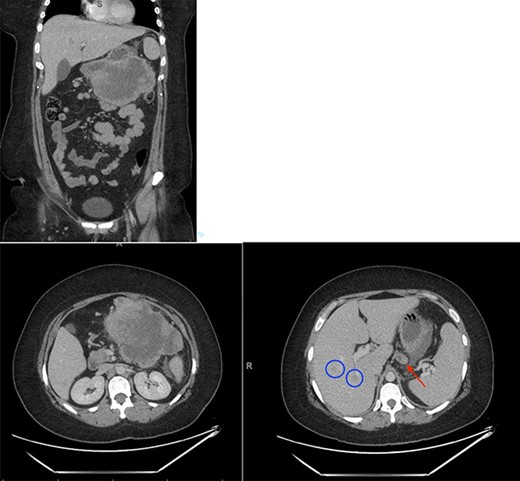

Investigations revealed an elevated WBC count of 35 × 10e9/L, a hemoglobin of 72 g/L and a CRP of 141 mg/L. A CT scan revealed a 15 × 11 cm multi-lobulated, heterogeneous, necrotic, exophytic mass arising from the stomach as well as multiple peritoneal deposits and five suspicious masses in the liver (Fig. 1). Upper endoscopy and liver biopsies were performed, and she was discharged home awaiting pathologic diagnosis. CT scan of her chest was negative for metastatic disease.

Initial CT scan showing large epigastric mass originating from the greater curvature of the stomach. Red arrow indicates large necrotic lymph node. Blue circles indicate liver metastases.